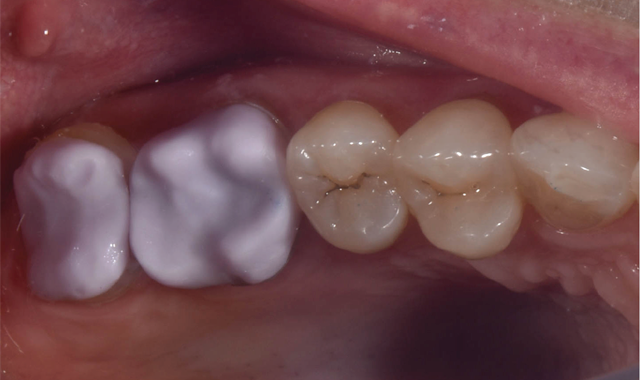

A 50-year-old female with no significant medical history presents for same-day, all-ceramic, full coverage onlay restorations on tooth No. 14 and No. 15. Existing restorations include No. 14OL and No. 15DO defective composites with open margins and recurrent caries (Fig. 1). The patient reports infrequent cold sensitivity localized to No. 14 and No. 15.

Fig. 1 Fig. 2